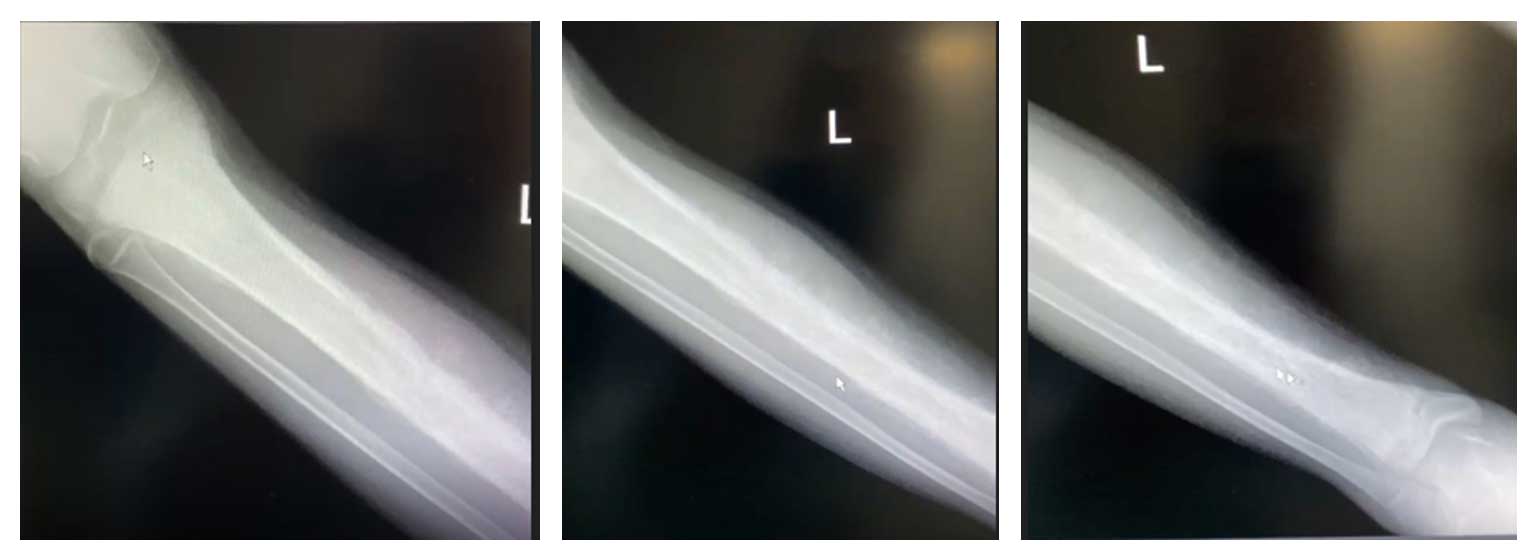

14 yaş erkek hasta, sağ kaval kemiğinde (tibia) ağrı ve şişlik şikayetleriyle başvurdu. Yapılan radyolojik incelemelerde tibianın büyük kısmını tutan osteosarkom saptandı.

Ameliyat Öncesi: Röntgende tibianın tamamına yakınını tutan düzensizlik, harabiyet ve güneş patlaması görünümde periost reaksiyonu.